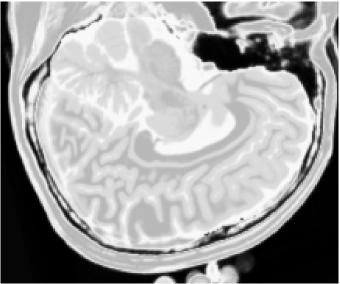

Figures 1 (band 0), 2 (band 1) and 3 (band 2) show PD- (proton density), - and -weighted MR images of the 97th slice, while figure 4 shows the R0-G1-B2 colored composition of the same slice.